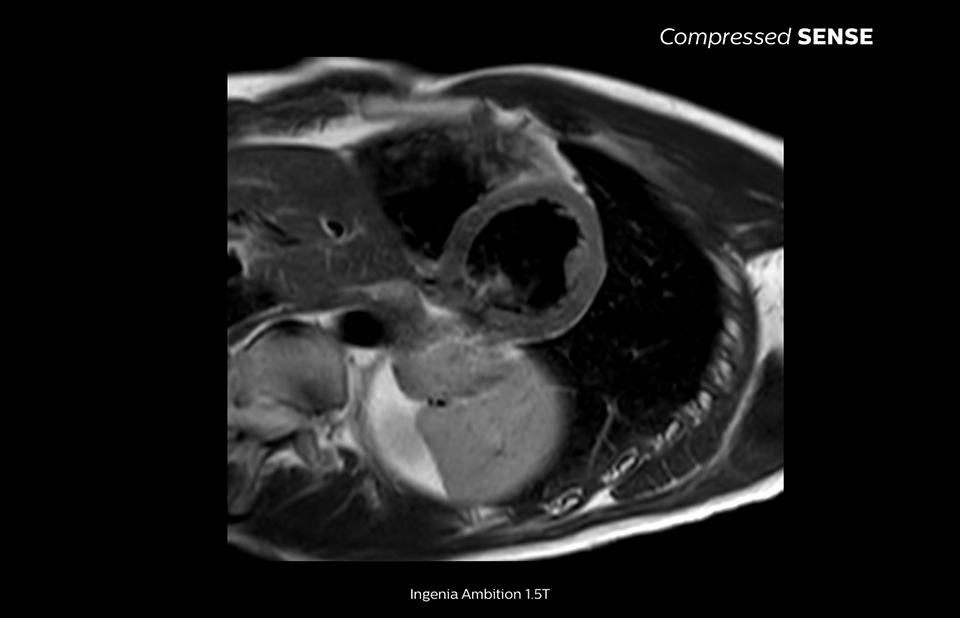

Philips Compressed SENSE reduces the time spent in the MRI scanner for the patient. Furthermore, Compressed SENSE enables the reduction of breath hold times which has the potential to improve compliance with an MRI scan.

4.8 sec breath hold time

Since short breath hold times make it easier for our patients to comply, the failure of breath holding largely disappeared.

At our facility, we found in Cardiac MR fewer breath holds are now needed, or breath hold times are shortened."

Dr. Takashi Koyama, MD, PhD, Diagnostic Radiologist and Director of the Department of Radiology Center and Diagnostic Radiology, Kurashiki Central Hospital, Japan

A 15- or 16-second breath-hold is tough for many cardiac patients. With Compressed SENSE we actually have protocols now that can get that below 10 seconds. It’s a lot easier to get through for a patient, and patients are a lot more satisfied with the experience.”

Trevor Andrews, Ph.D., MR Physicist, University of Vermont Medical Center, USA

The MRI staff at Kurashiki Central Hospital incorporated Compressed SENSE into most of the brain, spine, abdominal, and cardiac examination protocols on their Ingenia 1.5T, resulting in fast and high-quality MRI scans, which is welcomed by patients and staff.